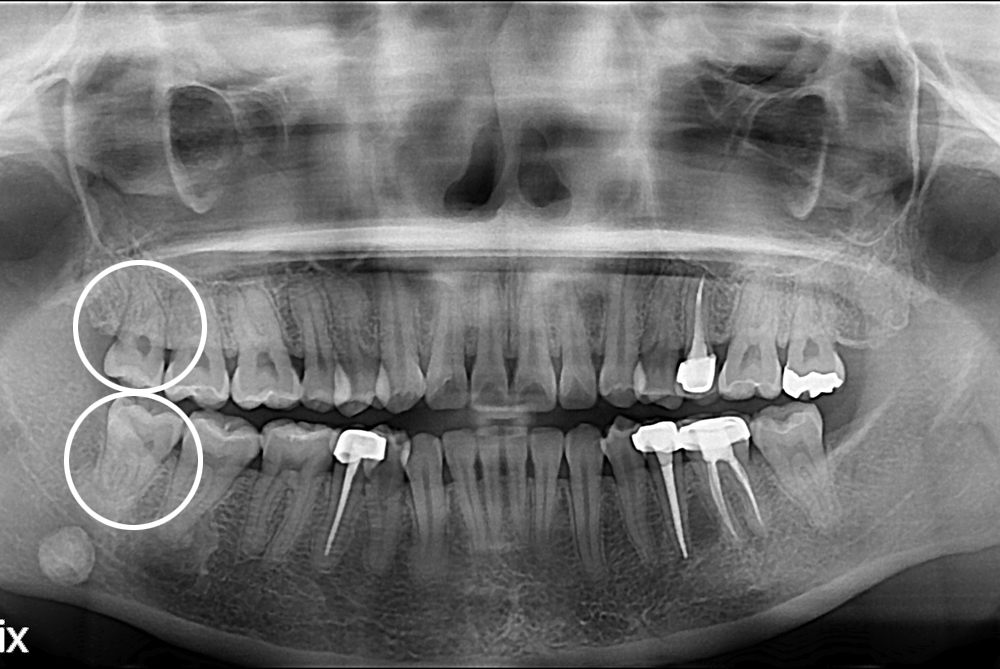

[사랑니] 난발치 사랑니 발치

치료전 : 2017-03-09

세종치과는 구강악안면외과학 박사이신 원장님이 발치하는 치과입니다.